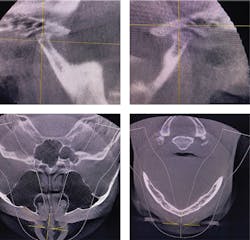

Airway/breathing disorders:Positive—imaging (CBCT deviated septum, narrow posterior airway; figure 3); Negative—overnight pulse oximetry

TMD/occlusion disorders:Positive—Doppler auscultation (joint crepitus), imaging severe joint degeneration (figure 3)